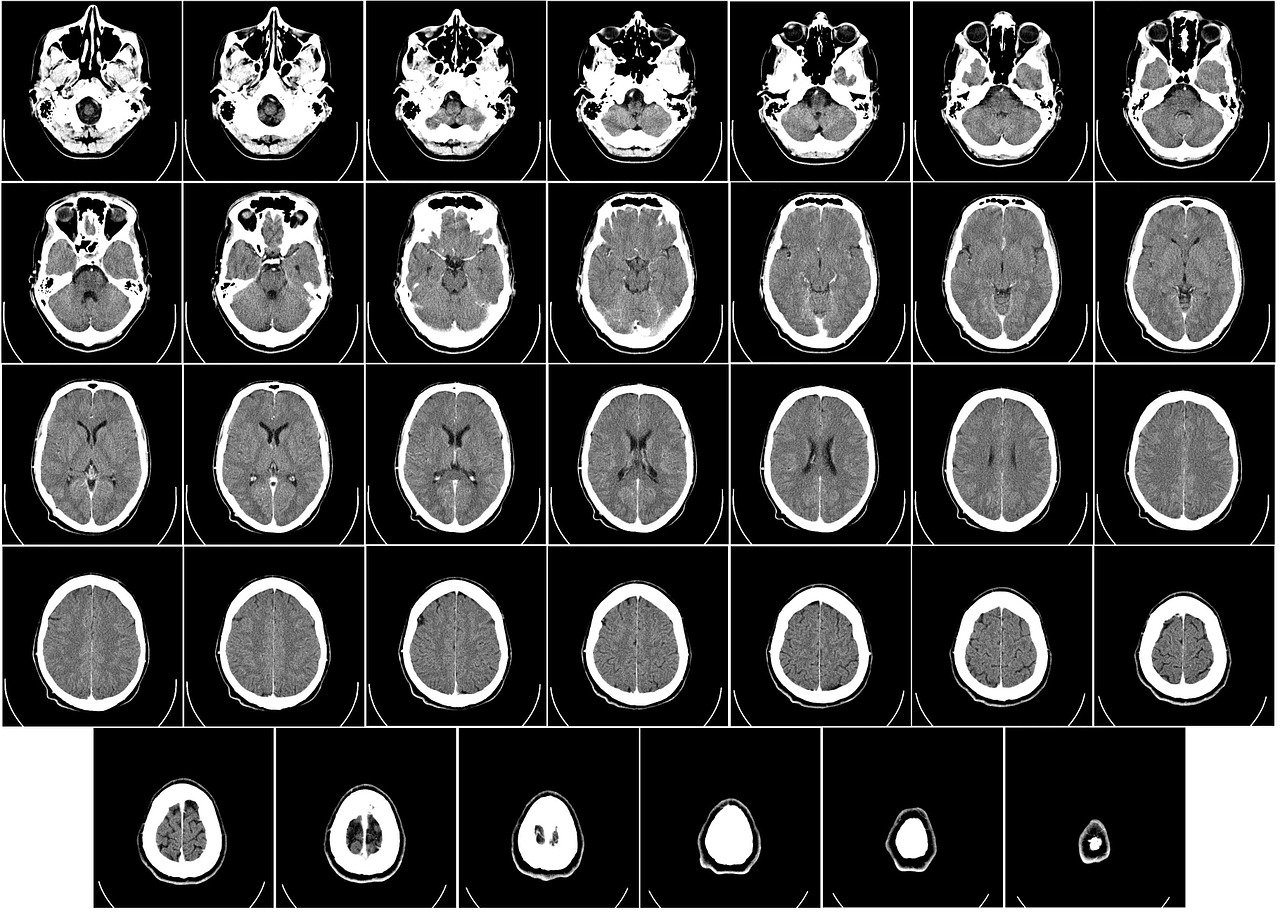

1. 뇌 CT

뇌 CT는 전산화 단층 촬영으로 뇌졸증이나 뇌종양, 뇌부종 등의 이상적인 증상을 초기에 확인할 수 있습니다. 보통 응급으로 뇌 상태를 확인하거나 뇌질환의 초기 증상이 의심될 때 사용되는 검사입니다. 머리에 충격이 가해지는 등의 사고로 인해 뇌진탕이나 뇌출혈이 의심될 경우 빠른 진단을 위해 검사를 뇌 CT 검사를 먼저 합니다. 또한 뇌경색의 초기증상인 얼굴이나 신체의 일부가 마비되는 느낌을 받았을 때 뇌 CT로 먼저 확인을 할 수 있습니다. 다만 단점이 해상도가 낮기 때문에 뇌혈관까지는 정밀하게 보기 힘들다는 것인데요. 시간이 적고 비용이 저렴한 편이라서 초기 검사용으로 많이 사용됩니다.